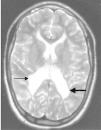

Introducción: Se han descrito episodios de manía-hipomanía en un 7% de los niños con déficit del neurodesarrollo. El retraso mental, motor y del lenguaje son factores de riesgo para enfermedad bipolar. Caso clínico: Describimos a un adolescente de 17 años con diplejía espástica por asfixia perinatal, retraso mental grave y déficit visual, sin historia psiquiátrica previa. Su padre padece enfermedad bipolar. Presenta, bruscamente, insomnio global de 8 días de duración, inquietud creciente, apatía y anhedonia. Mejora con lorazepam (1 mg), y trazodona (100 mg/día) en 3 meses, con remisión del cuadro. A los 12 meses presenta, de nuevo bruscamente, insomnio global de 14 días, logorrea e inquietud psicomotriz, por lo que se reinicia la administración de lorazepam y trazodona. Aparecen desorientación, alucinaciones y mayor inquietud. Mejora con olanzapina (2,5 mg/día). Persisten la agitación y las alucinaciones, que se alternan con apatía y anhedonia en un mismo día. Se inicia el tratamiento con valproato sódico intravenoso (16 mg/en 1 h), luego oral, con mejoría del cuadro en la primera semana tras el valproato oral (20 mg/kg/día). Hay un buen contacto con el medio y lenguaje coherente hasta 1,5 años tras el inicio de esta medicación. Discusión: El diagnóstico de manía es especialmente difícil en adolescentes con retraso motor, intelectual o déficit visual. La ciclación rápida, la carga genética y la respuesta a estabilizadores del humor apoyan el diagnóstico.

Introduction: Mania-hypomania has been described in 7% of children with neurodevelopmental delay. Mental, motor and language retardation are all risk factors for bipolar disorder. Case report: We describe a 17-year-old boy with spastic diplegia, severe mental retardation, and visual deficit due to perinatal asphyxia, with no previous psychiatric history. His father has bipolar disorder. Our patient suddenly developed a first episode of global insomnia (lasting 8 days), prominent logorrhoea, psychomotor agitation, apathy and anhedonia. He improved with lorazepam (1 mg) and trazodone (100 mg/day) in 3 months, achieving complete remission of symptoms. Twelve months later, he suddenly developed global insomnia again (lasting 14 days) and restlessness. Lorazepam and trazodone were prescribed again. A few days later, he developed confusion, delusions and increased psychomotor agitation. The patient improved with olanzapine (2.5 mg/day), but his restlessness and delusions, which alternated with apathy and anhedonia in the same day, continued. Intravenous valproate (16 mg in 1 h) was started, followed by oral administration of oral valproate (20 mg/kg/day), with marked improvement of symptoms during the first week. He has been stable after 1,5 years of treatment with oral valproate monotherapy. Discussion: The diagnosis of mania is particularly difficult in adolescents with mental, motor and visual deficits. Rapid cycling, genetic factors and mood stabilizer response indicate a probable diagnosis of mania.